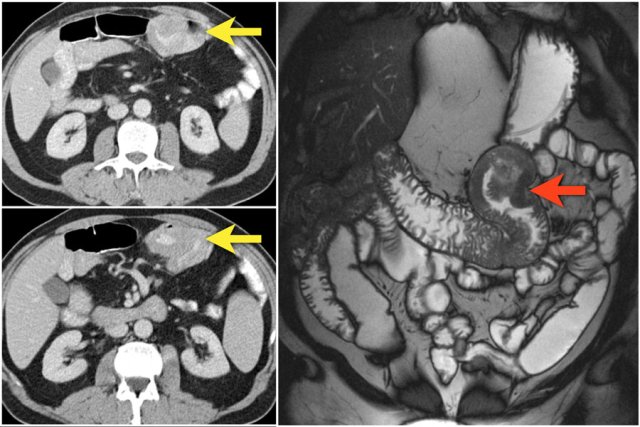

Here another adenocarcinoma located in the jejunum.

There are multiple lymph nodes (red arrow) and there is fat stranding (yellow arrows).

It should not be mistaken for mesenteric panniculitis as these large necrotic lymph nodes are pathologic.